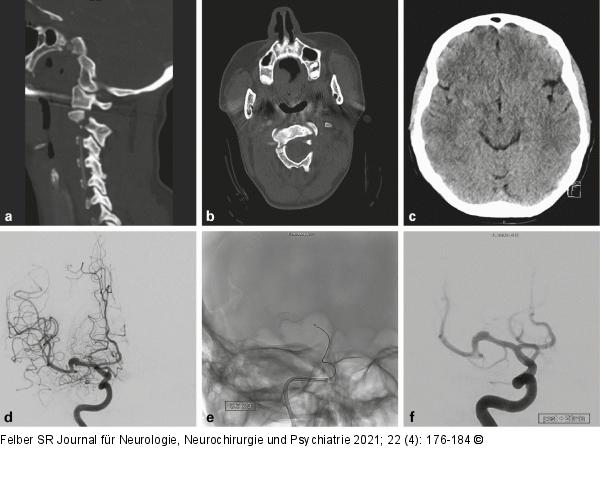

Abbildung 1a-f: Dissektionsaneurysma Die 54-jährige Patientin erlitt bei einem Verkehrsunfall eine HWK-2-Fraktur (a, b) und eine Commotio cerebri. Das zerebrale CT zeigte in der Sylvische Fissur eine kleine umschriebene Hyperdensität (c). Angiographisch fand sich ein fusiformes Dissektionsaneurysma der rechten Arteria cerebri media (d). Das Aneurysma wurde durch zwei flusskorrigierende Stents (e, f) behandelt (p64 3,5 × 21 mm und p64 3,5 × 9 mm, Phenox, Bochum, Deutschland) und bildete sich in der Folge vollständig zurück. |

Abbildung 1a-f: Dissektionsaneurysma

Die 54-jährige Patientin erlitt bei einem Verkehrsunfall eine HWK-2-Fraktur (a, b) und eine Commotio cerebri. Das zerebrale CT zeigte in der Sylvische Fissur eine kleine umschriebene Hyperdensität (c). Angiographisch fand sich ein fusiformes Dissektionsaneurysma der rechten Arteria cerebri media (d). Das Aneurysma wurde durch zwei flusskorrigierende Stents (e, f) behandelt (p64 3,5 × 21 mm und p64 3,5 × 9 mm, Phenox, Bochum, Deutschland) und bildete sich in der Folge vollständig zurück. |